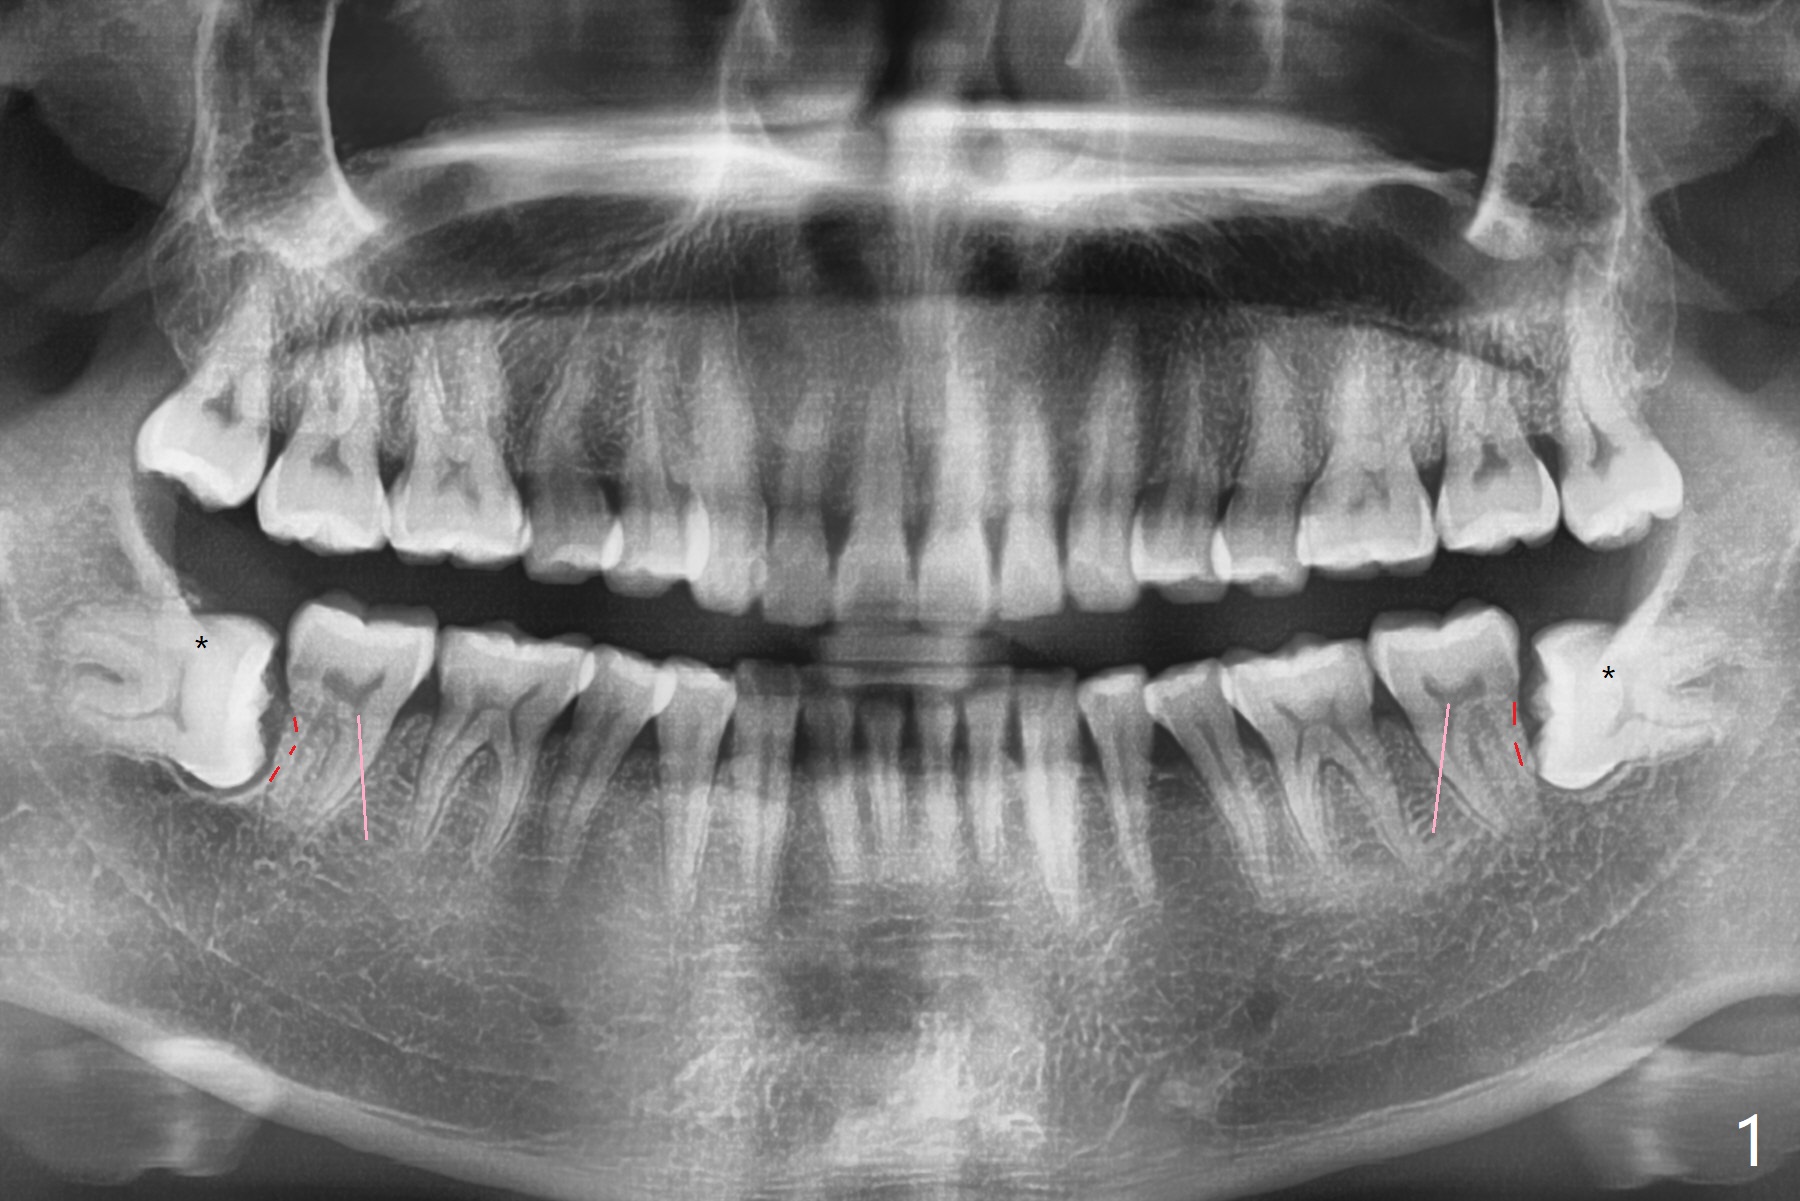

30岁男第一次看牙医,主诉:左下智齿食物坎塞,口臭,牙龈出血。为了促进第二磨牙远中骨质再生,拔除下颌智齿后,植入粘性骨粉或者异体骨加GEM21S。智齿好像有些颊侧阻生(图一:红虚线),斜型附加切口偏7近中(粉红色)。外斜嵴(*)似乎没有完全形成。